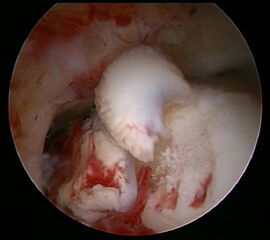

Ein aktuelles systematisches Review zur arthroskopisch-assistierten Frakturversorgung (AORIF) am Sprunggelenk identifizierte bei 495 von 782 Patienten (63,3%) chondrale Verletzungen 54. Weder durch die klinische Untersuchung noch mit konventionellen Röntgenaufnahmen oder mittels CT-Bildgebung lassen sich diese Verletzungen zuverlässig diagnostizieren. Aus diesem Grund rückt die arthroskopisch-assistierte Frakturversorgung am oberen Sprunggelenk zunehmend in den Fokus. Die Arthroskopie ermöglicht im Rahmen der Frakturversorgung sowohl die Kontrolle der Reposition als auch die Beurteilung und Therapie von intraartikulären Pathologien. Während sich die arthroskopisch-unterstützte Versorgung einiger Frakturen bereits etabliert hat (z.B. proximale Tibiafraktur) gehört der Einsatz der Arthroskopie bei der Frakturversorgung des oberen Sprunggelenks in den allermeisten Kliniken noch nicht zum Versorgungsalltag 155 Im Gegenteil, in einer aktuellen amerikanischen Datenbankanalyse des United Healthcare Orthopedic Datasets wurden zwischen 2007 und 2011 insgesamt 32 307 Patienten identifiziert, die mittels ORIF an einer Sprunggelenksfraktur versorgt wurden. In weniger als einem Prozent erfolgte eine arthroskopisch-assistierte Versorgung 55. Dem gegenüber stehen arthroskopische Studien der vergangenen Jahre, die zeigen konnten, wie häufig es zu intraartikulären Verletzungen bei Sprunggelenksfrakturen kommt. Das Risiko für diese intraartikulären Begleitverletzungen nimmt mit der Komplexität der Fraktur zu 5657. Es liegt also nahe, dass bei komplexeren Frakturen die Durchführung einer Arthroskopie im Rahmen der Frakturversorgung einen positiven Effekt auf das Behandlungsergebnis hat. Aus Sicht der Autoren sollte es Ziel für die Zukunft sein, die Frakturtypen zu identifizieren, die von einer arthroskopisch-assistierten Frakturversorgung profitieren. Die diagnostische Arthroskopie mit dem Ziel der gleichzeitigen arthroskopischen Therapie ist in der aktuellen S2-Leitlinie bereits eine Level-1b-Empfehlung. In den Abbildungen 20 – 30 ist schrittweise unser Vorgehen zur arthroskopisch assistierten Versorgung einer Trimalleolarfraktur dargestellt.